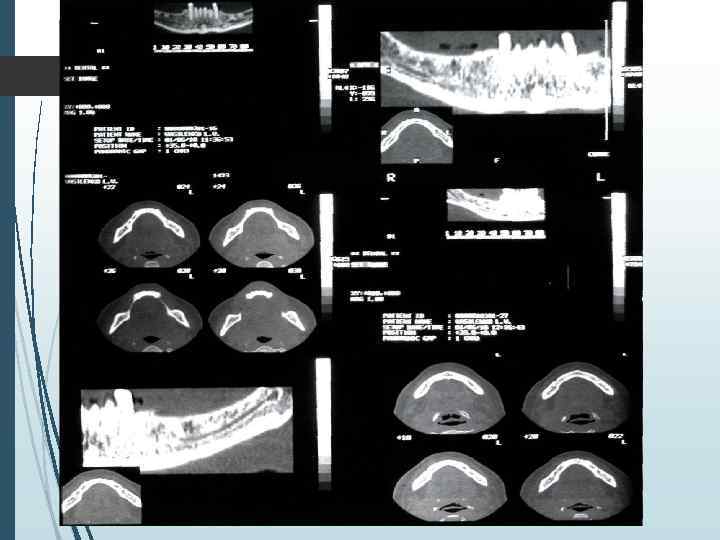

Компьютерная томография является одним из наиболее информативных методов рентгенологического обследования. С высокой степенью достоверности она позволяет определить высоту и ширину кости, топографию нижнечелюстных каналов и верхнечелюстных пазух, особенности архитектоники различных отделов челюстей, соотношение последних, а также создать трёхмерное изображение лицевого отдела черепа